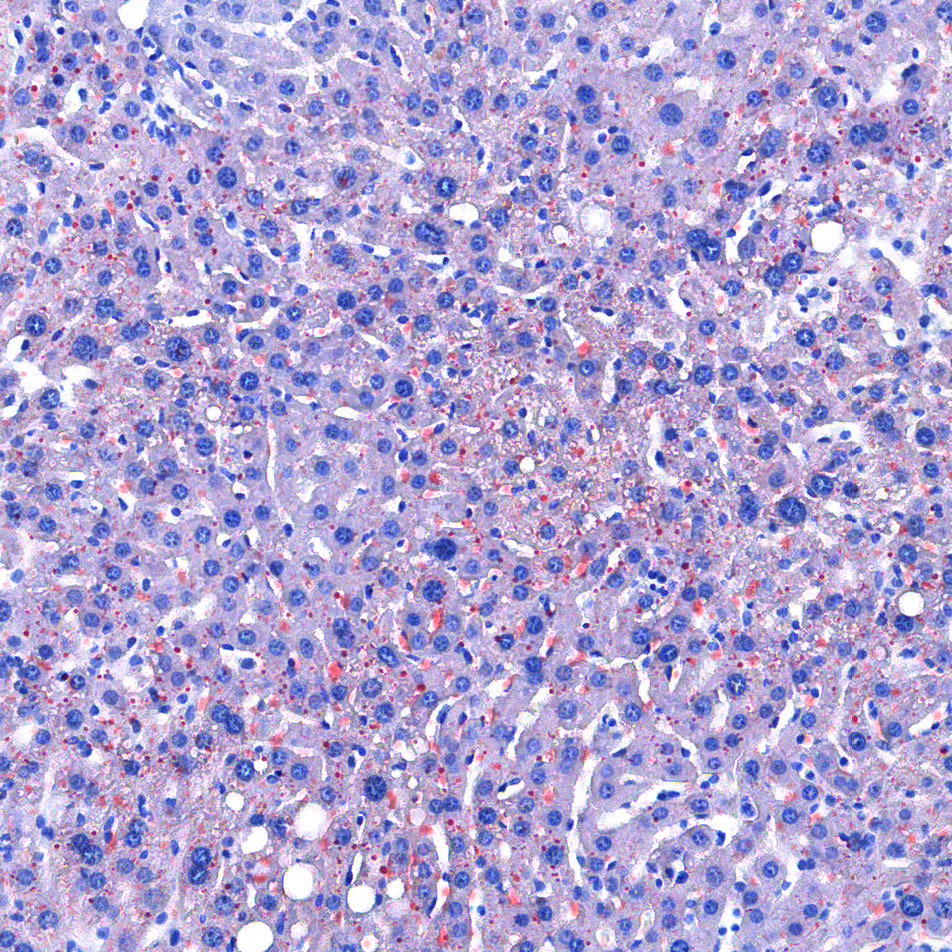

实验结果展示:

<油红O-肝>